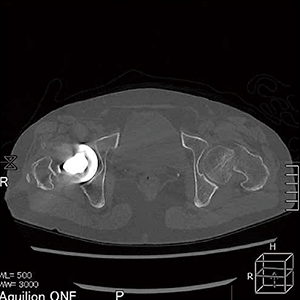

■症例3:左骨頭骨折症例

左骨頭骨折が明瞭に描出されている。